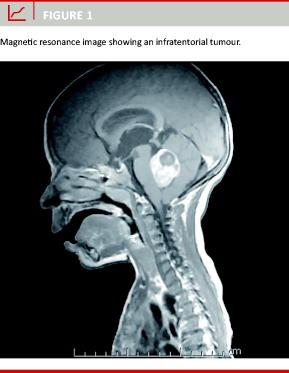

The presenting symptoms and signs are dependent on localisation with ataxia, cerebral nerve deficits and gait abnormalities present in infratentorial tumours (Figure 1), along with motor dysfunctions, seizures, visual dysfunctions and endocrinological abnormalities as the most frequently seen supratentorial localisations [2]. Symptoms of increased intracranial pressure with headache and vomiting, together with papilloedema, develop more rapidly in infratentorial tumours than at other localisations due to their proximity to the fourth ventricle.